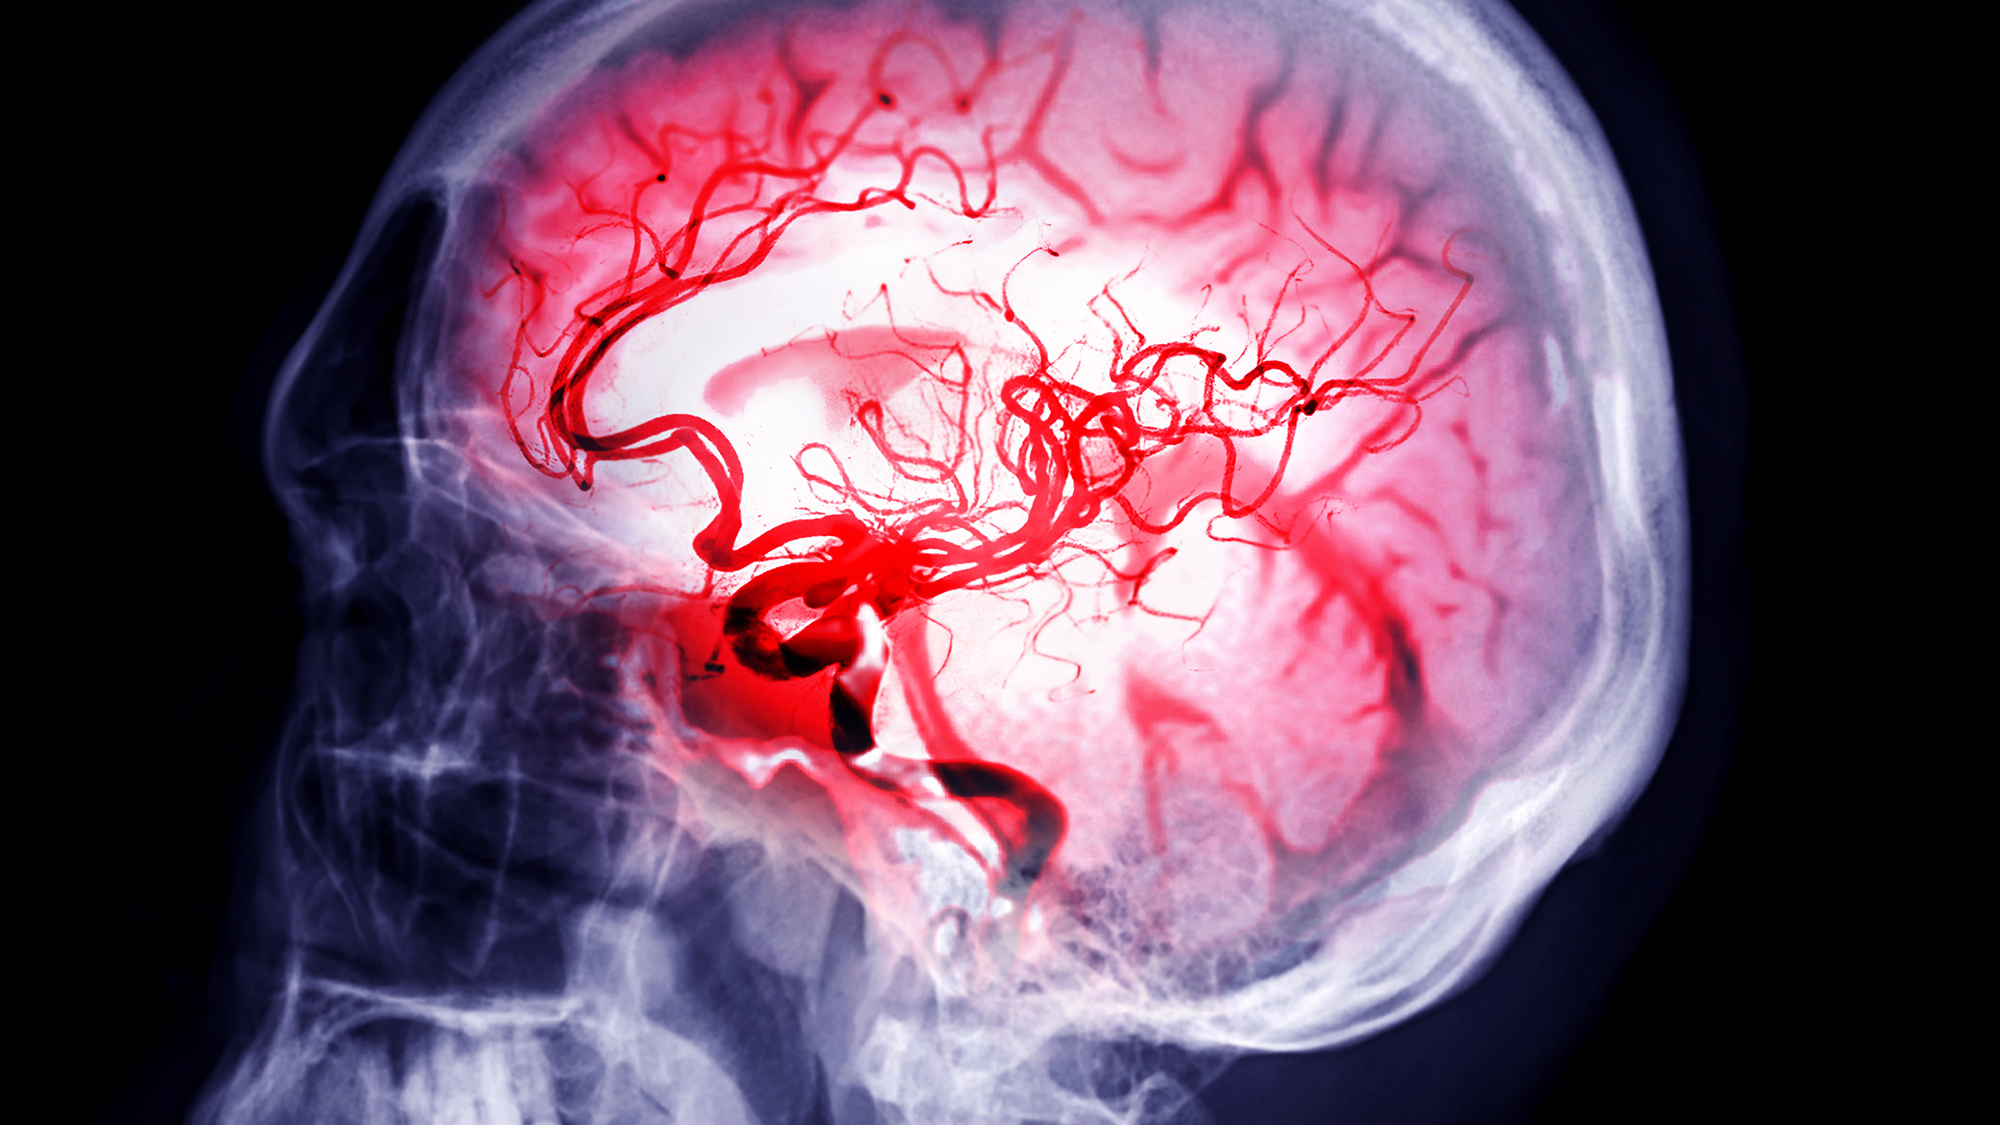

Инсульт: малоизвестные факты, которые могут спасти вашу жизнь

Инсульт окружен мифами о том, что это «болезнь стариков» или что он всегда сопровождается параличом половины тела. На самом деле это состояние гораздо коварнее. Вот пять не самых очевидных, но жизненно важных фактов.